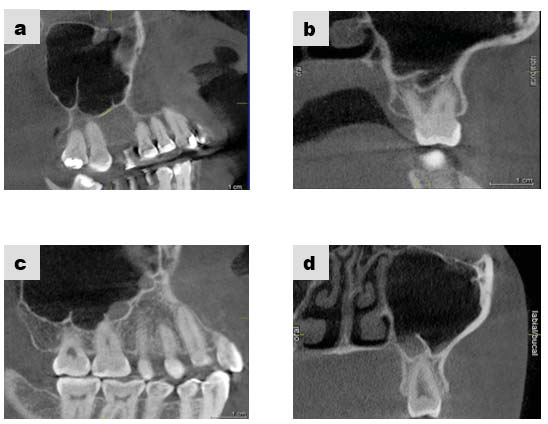

Los septos suelen ser crestas óseas puntiagudas o con forma de arco gótico (6,7,8,9) que se ubican en el seno maxilar, generalmente son hallazgos radiológicos, son de tamaño variable llegando incluso a dividir el seno completamente en dos o más cavidades (1, 2,10-13), su diagnóstico diferencial son las exostosis, sin embargo éstas tienen forma redondeada (6,7,8) (figura 1).

De acuerdo a su origen, existen dos tipos de septos: los primarios y los secundarios. Los primarios o llamados también septos congénitos, se forman durante el desarrollo de la zona central de la cara, originándose de la fusión de residuos durante la formación del seno maxilar (12), (figura 2 y 3); sin embargo Underwood relaciona su origen con las piezas dentarias justificando que se forman por separaciones intermedias del piso antral debido al desarrollo radicular (14). Autores como Lee et al., mencionan que los septos se originan por proyecciones digitales debido a la invaginación del infundíbulo etmoidal durante el desarrollo embrionario donde las paredes adyacentes no se reabsorben (2).

Los septos secundarios, tienen un origen adquirido asociado a atrofia del hueso maxilar como consecuencia de pérdida de dientes, siendo más frecuentes en el piso del seno. La longitud de éstos septos suele ser inferior que los primarios (2,7,12,15,16,17,18). (figura 4 y 5). Gonzales et al., consideraron septos primarios a aquellos donde hay piezas dentarias presentes y los septos secundarios en zonas edéntulas (6).

En este trabajo de investigación se evaluaron 458 septos, mediante TCV considerando pacientes de ambos sexos, con edades de 18 años a más, las características que se consideraron fueron: tipo de septo (congénito u otros septos), localización (bilateralidad y lado), longitud (es la medida del septo desde la unión de los lóbulos del seno maxilar hasta su porción más distal). La finalidad de este reporte fue revisar los rasgos tomográficos de los septos en el seno maxilar para que no pasen desapercibidos por los cirujanos maxilofaciales, implantólogos y periodoncistas, ya que la presencia de uno o más septos implica realizar cambios en la angulación de los implantes dentarios (1-3,5,7,12), así como la creación de más de una ventana quirúrgica en los procedimientos de elevación de seno maxilar, para evitar la perforación de la membrana de Schneider (13,16,17,19,20).